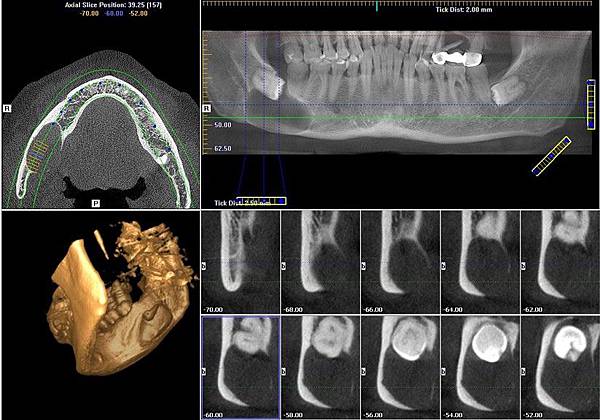

@分享一個case治療 (以下供專業人士參考)

@治療: (感謝聖馬爾定口腔外科主任李芳輝醫師建議)

1. 太大的cyst, 非常靠近nerve, 手術後有很高的比例nerve會numbness。

2. 拿cyst時, 有bone的地方都簡單刮, 然後再往沒bone的地方刮, Lingual side 雖沒bone但還有骨膜, 往下撥就都撥到快神經位置, 最後再撥神經地方,基本上不會難撥,

若出血, 就iodoform 加gelform壓一段時間,

cyst到下面會覺得好像有一條靱帶的東西拉住,可以用peanuts或mosquito dissect

3. 囊腫刮除後考慮teruplug或surgiaid, 只要teruplug不要動來動去就OK了, 尤其是神經的位置放上gelform或teruplug做保護, 也可以加骨粉放在teruplug上方

##如果目前有pus, 就在神經上方放gelform, 再塞 iodoform, 避免神經與iodoform直接接觸, 術後兩個月再補骨+再生膜, 不補骨的話長得很慢 (理論上2周沒感染就可以補bone了, 但距上一次手術太近, p't可能還沒休息夠, 術後2個月再打開直接放bone, 因為wound還在healing中, bone會長得好一點

4. Flap關不起來,就翻大,release, 一定要能輕鬆縫好